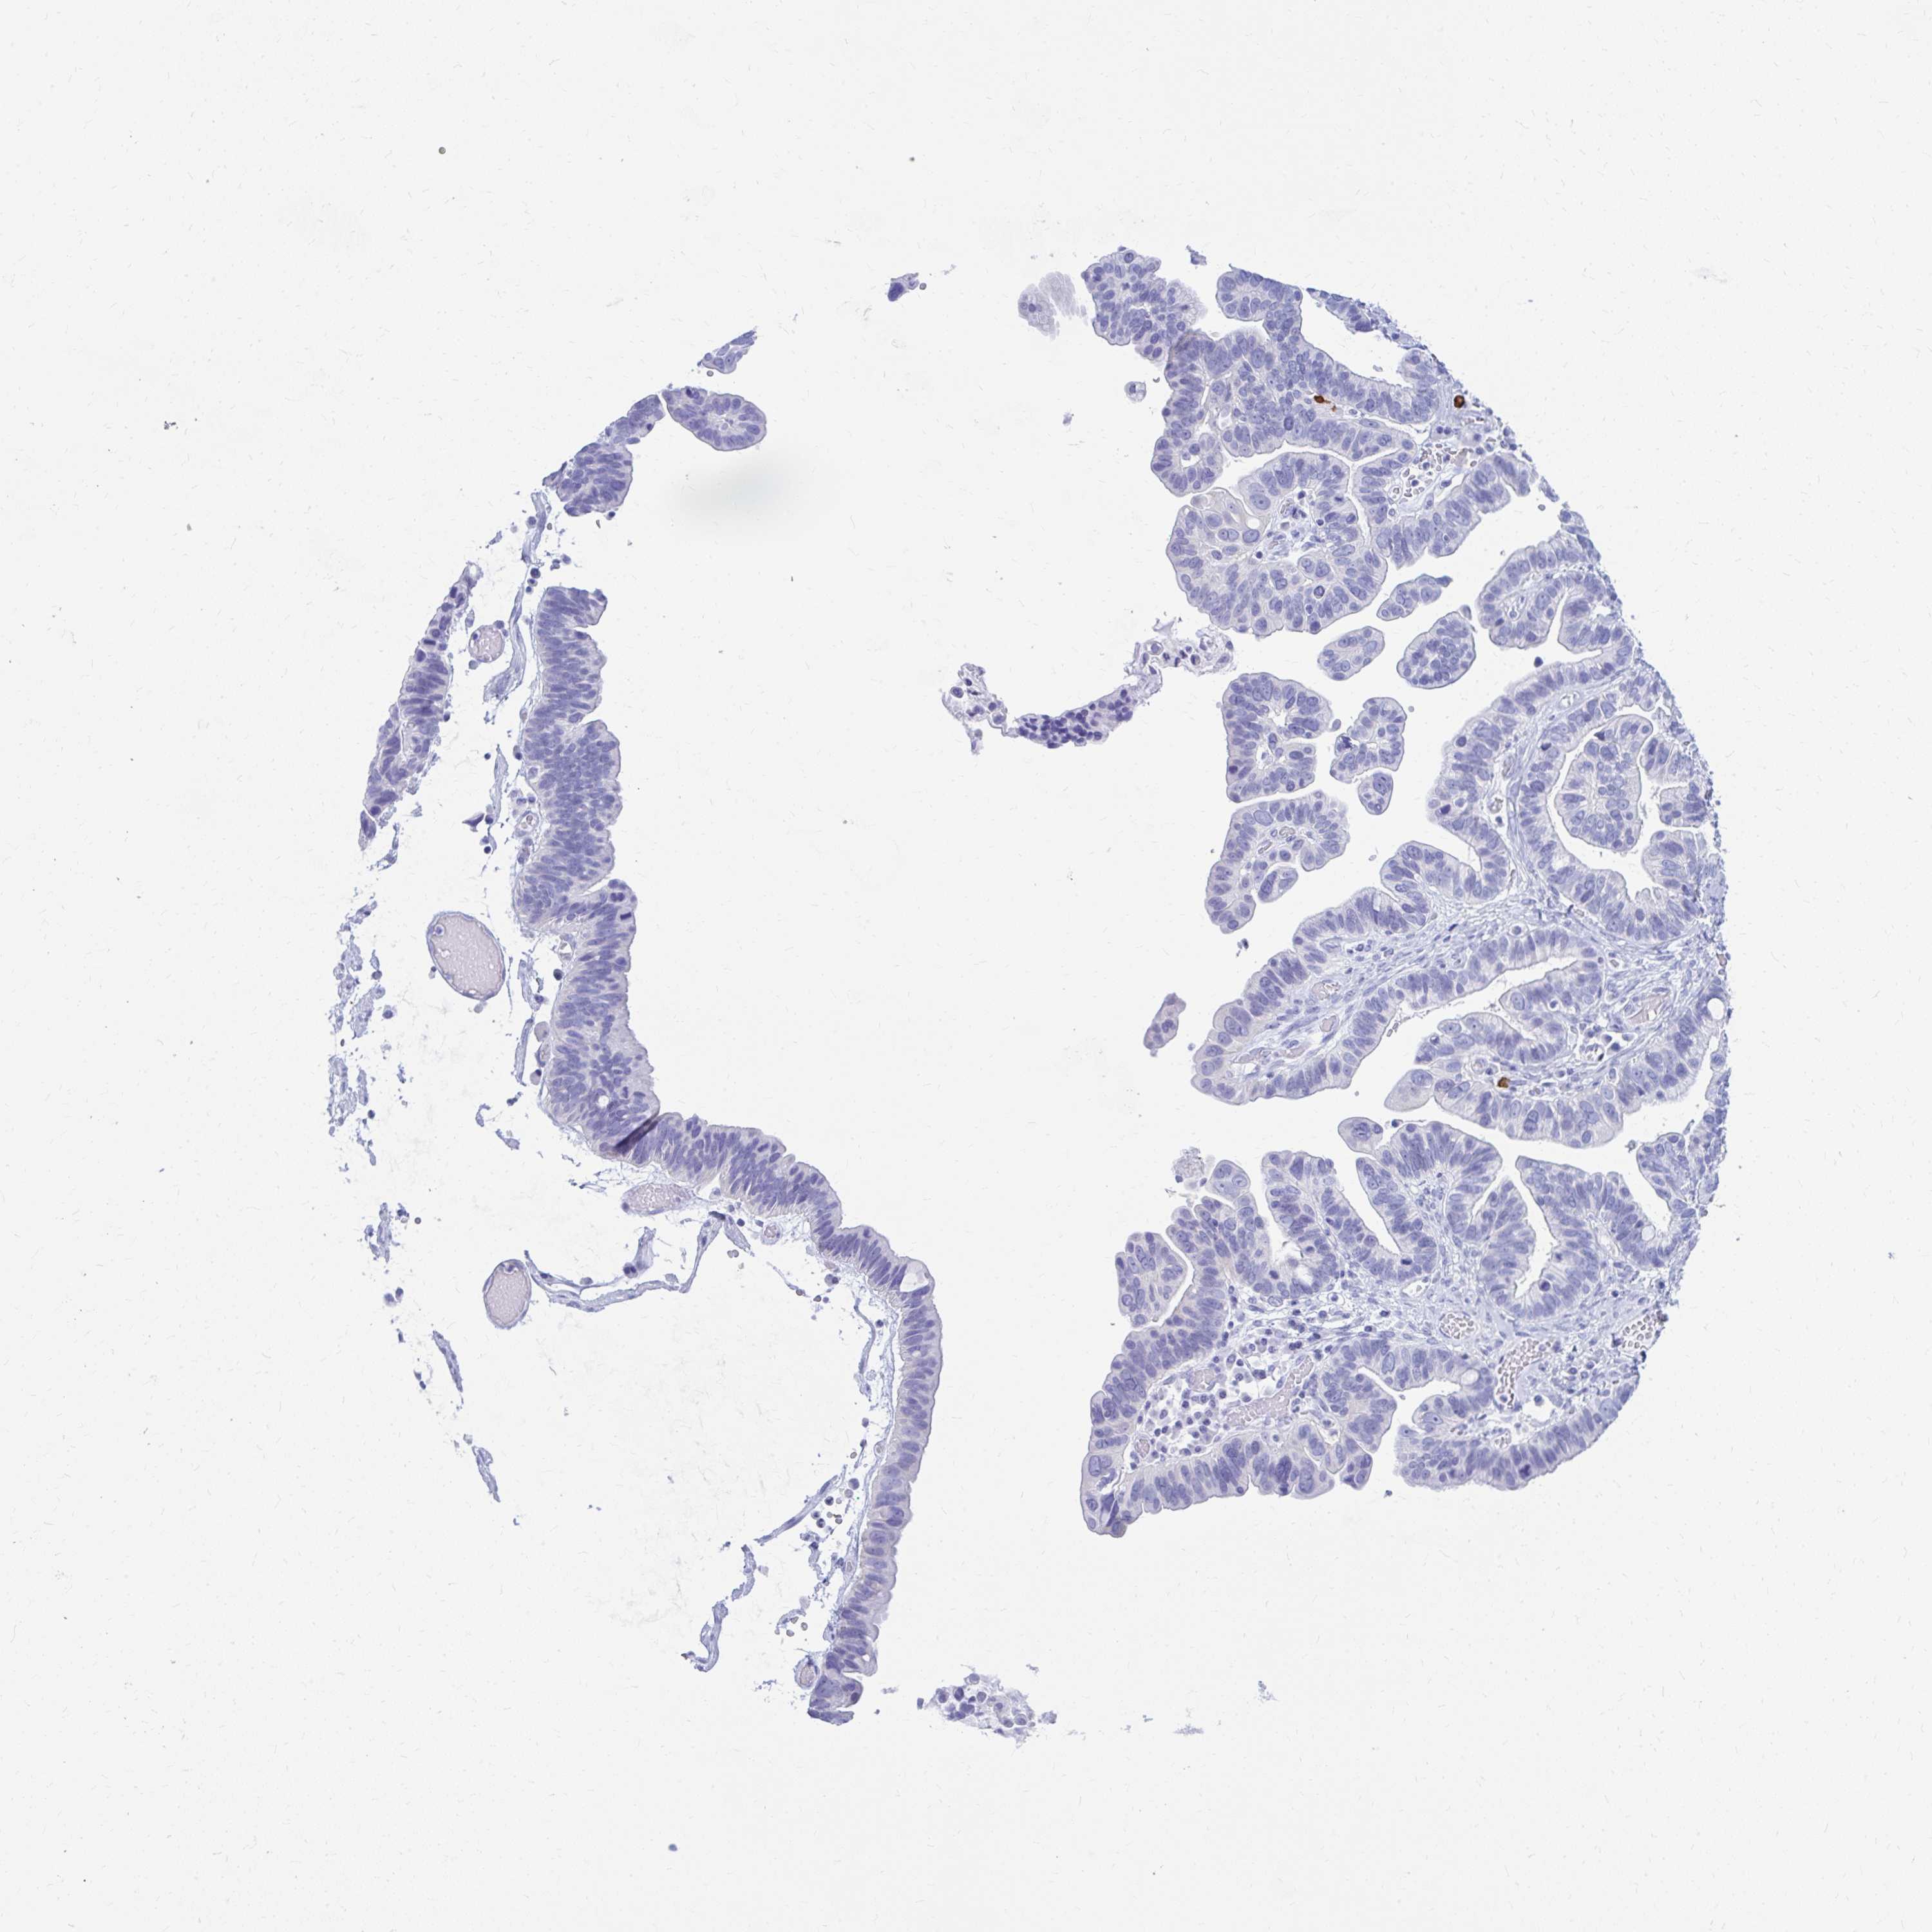

OVARIAN CANCER - Protein expressioni

A mouse-over function shows sample information and annotation data. Click on an image to view it in a full screen mode. Samples can be filtered based on level of antibody staining by selecting one or several of the following categories: high, medium, low and not detected. The assay and annotation is described here.

Note that samples used for immunohistochemistry by the Human Protein Atlas do not correspond to samples in the TCGA dataset.

Antibody stainingi

Antibody staining in the annotated cell types in the current human tissue is reported as not detected, low, medium, or high, based on conventional immunohistochemistry profiling in selected tissues. This score is based on the combination of the staining intensity and fraction of stained cells.

Each image is clickable and will lead to virtual microscopy that enables deeper exploration of all samples and also displays staining intensity scores, fraction scores and subcellular localization as well as patient and tissue information for each sample.

Antibody HPA056191

Cystadenocarcinoma, serous, NOS

Carcinoma, endometroid

Cystadenocarcinoma, mucinous, NOS

Carcinoma, NOS